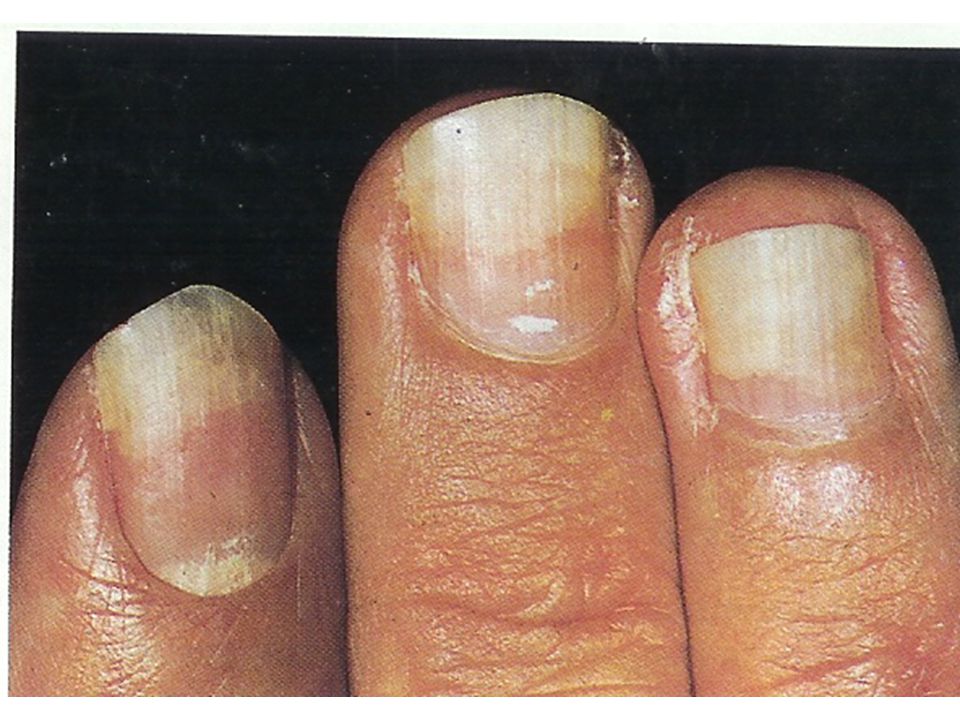

Грибковые заболевания ногтей: буклет с информацией